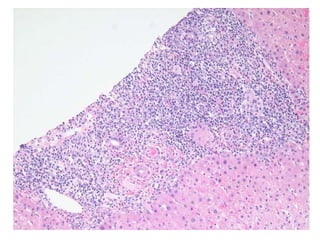

07-R-1192 Middle aged female with intractable pruritis.

S07-9238  Dx: Features compatible with primary biliary cirrhosis, Scheuer stage 1/4.

07-R-1192 Middle agedfemale with intractable pruritis.

S07-9238 Dx:Features compatible with primary biliary cirrhosis, Scheuer stage 1/4.